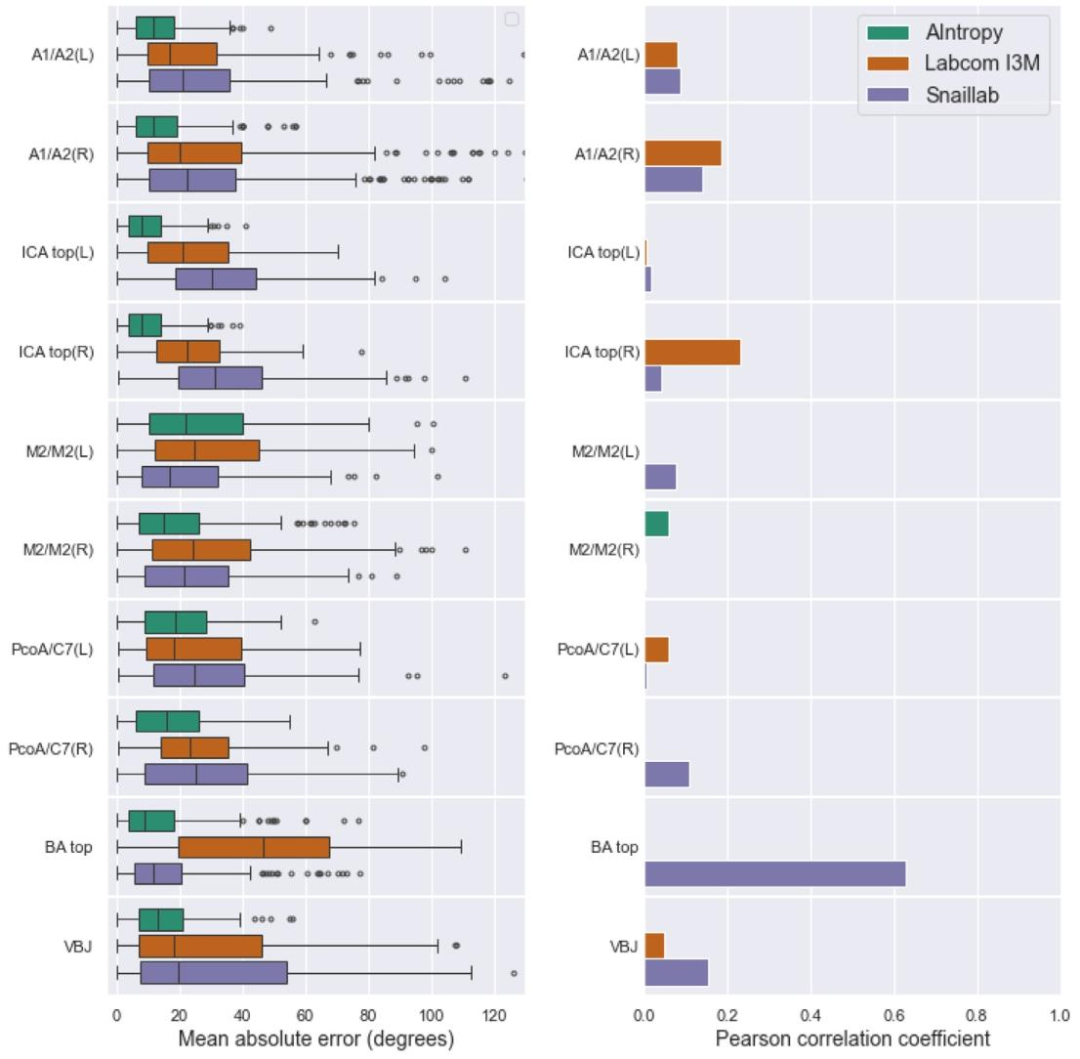

Fig. 7. Results of proposed solutions by each team for Task 2 (quantification of artery diameters and bifurcation angles) on the test set, shown per bifurcation. Lower meanabsolute error (MAE) and higher Pearson correlation coefficient are associated with better performance. The method of Labcom I3M yielded MAE scores exceeding 4.0 mm for allarteries except the BA.

图 7. 各团队针对任务 2(动脉直径和分叉角度量化)在测试集上按分叉处分类的结果平均绝对误差(MAE)越低且皮尔逊相关系数越高,表明性能越好。Labcom I3M 团队的方法中,除基底动脉(BA)外,所有动脉的 MAE 得分均超过 4.0 毫米。